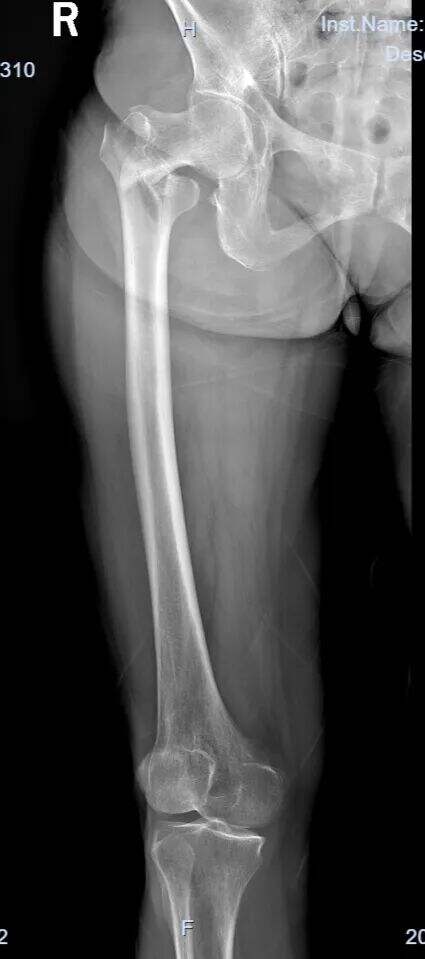

Starejša ženska, sprejeta po padcu.

Diagnoza: Pravi femoralni intertrohanterni zlom (AO razvrstitev tipa 31-A1.3).

Pri zlomih tipa 31-A1.3 je doseganje zadovoljive zmanjšanja vedno bilo izziv.